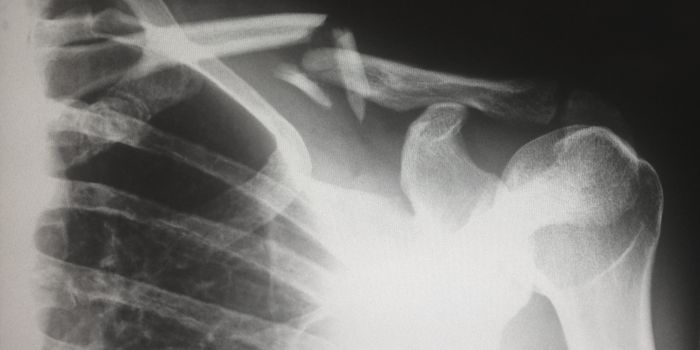

DEC 22, 2019Clinical & Molecular DXPatients presenting with severe coughs, chest pain or suspected infections are more than likely to be sent for a chest X ...

OCT 29, 2021TechnologyWe’re all familiar with x-rays—they’re a staple in diagnostic technology. The use of x-rays for medica ...

NOV 26, 2020Clinical & Molecular DXNew research has revealed that exposure to radiation from diagnostic procedures such as X-rays could contribute to an el ...